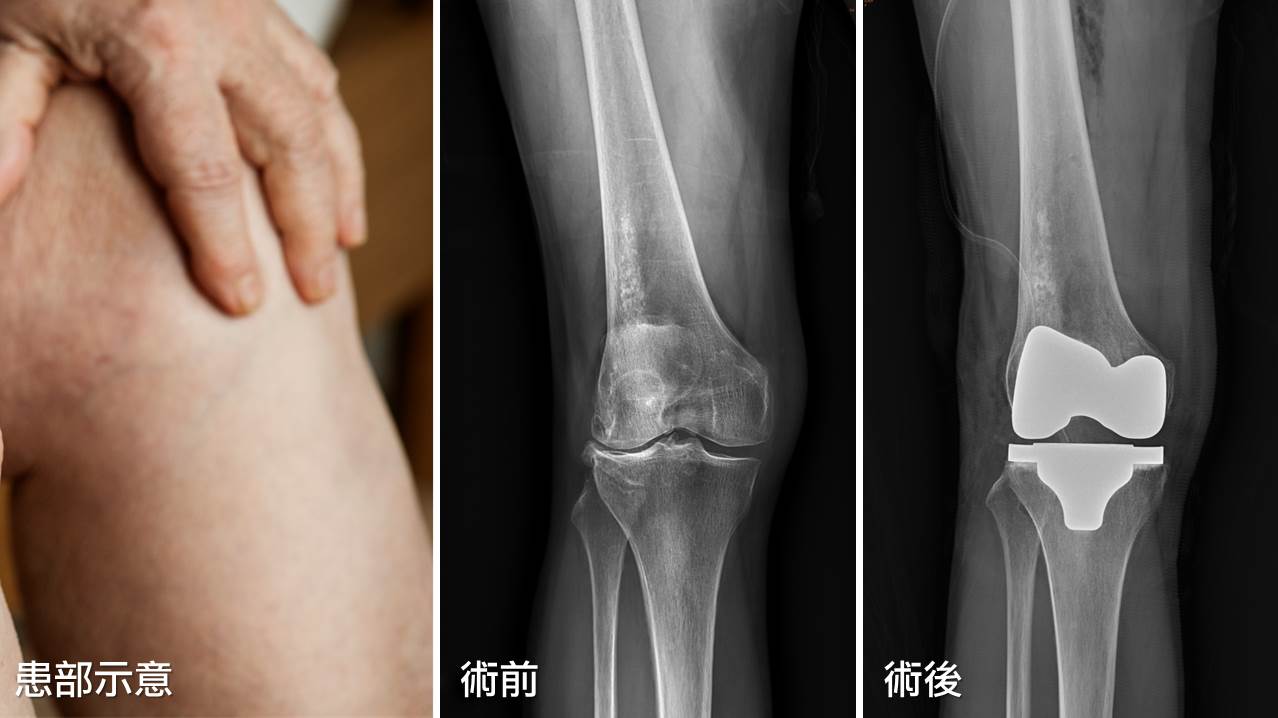

75歲的李阿姨,近幾年飽受膝關節疼痛之苦,爬樓梯更是辛苦,讓李阿姨都不敢出門,求診後才發現是膝關節退化,關節都磨損了,直到接受全膝關節置換術後,終於找回了活動力。

關節是人體活動的必要構造,當因為關節炎或其他原因造成磨損、進而感到疼痛,就會影響日常生活。如果保守療法不能達到預期的效果,人工關節置換往往是最後的治療。1974年骨科發展出了符合人體解剖構造的人工膝關節,自此,不論是在植入物的製造材料或是手術技術上都開始突飛猛進。

膝關節置換的最新進展為「客製化切模」,針對變形較嚴重的病患,利用影像翻模出病患本身關節的3D模型,可預先於電腦上計算精確的矯正角度及切除骨頭的範圍,大大降低術中人為的誤差。另一項進步則為機器手臂的使用,一樣可事先於電腦上計算精確的角度及切除的範圍,利用機器手臂的穩定度來增加切除的精準度,但目前價格仍相當高昂,未來若能普及,相信可造福更多病患。